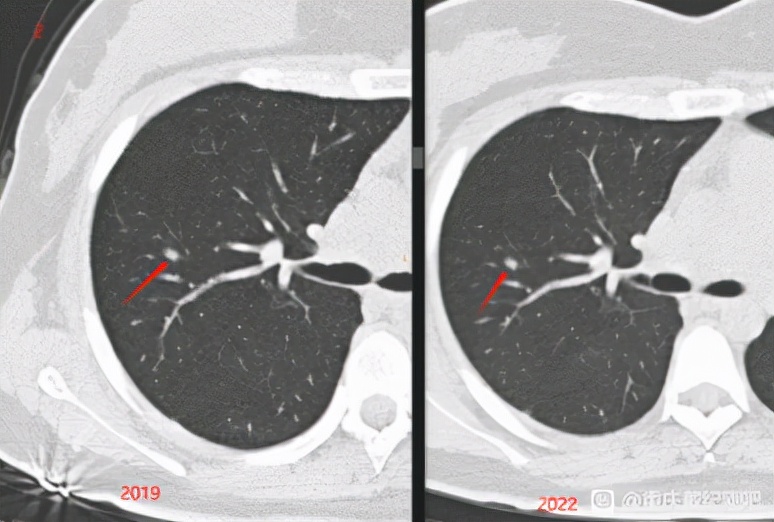

这是2019.9和2022.2在同家体检机构的CT对比: